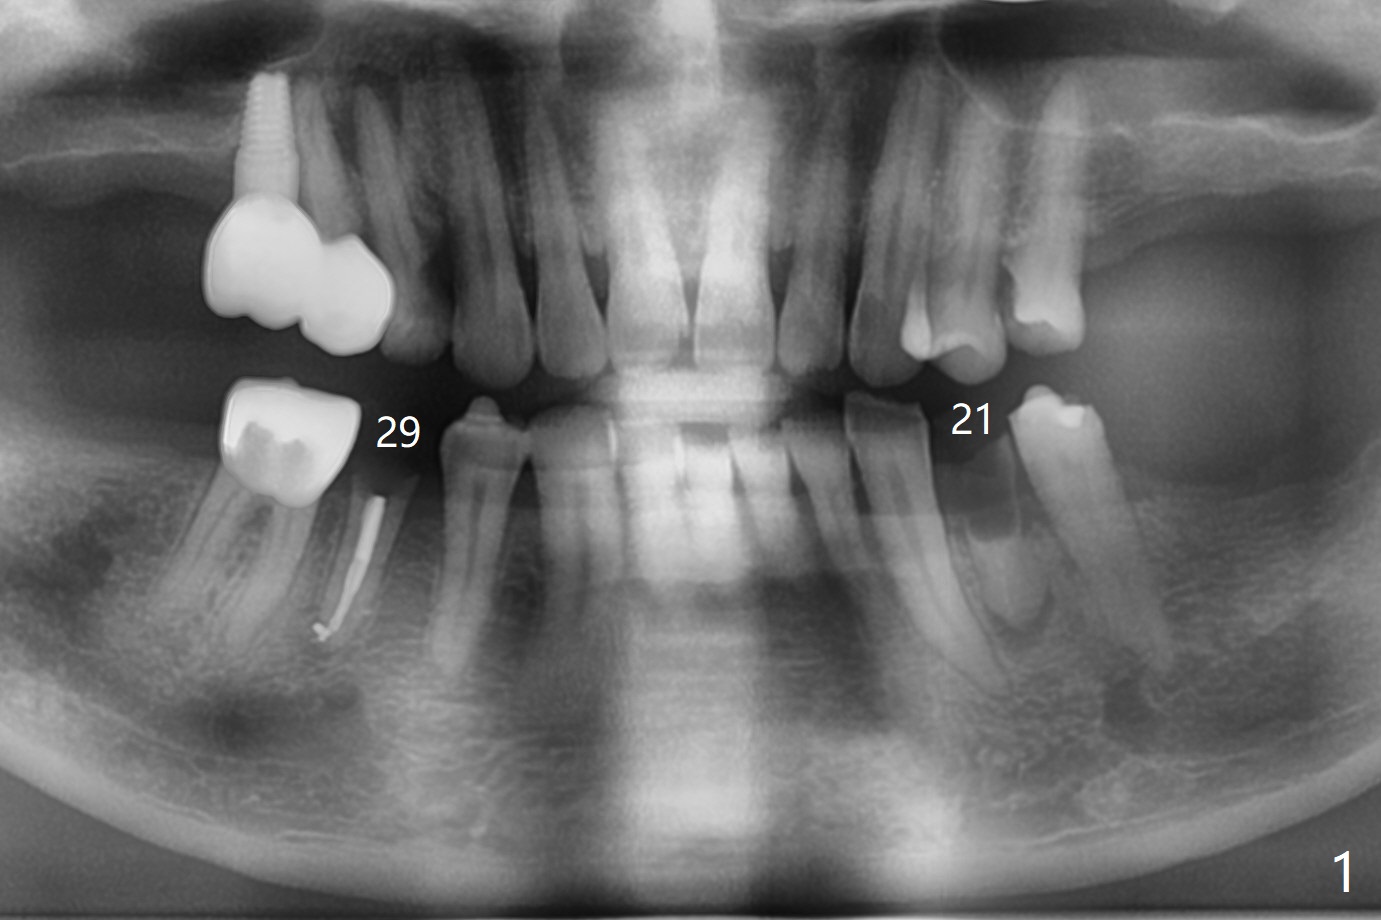

A 52-year-old man chooses to take care of the teeth #21 and 29 first due to finance (Fig.1). The implant diameter should not be too large because of the moderate mesiodistal space (Fig.2,3). Since the buccal plate of #21 is indistinct (socket shield will be done), the implant should be a little more lingually placed than the design in Fig.3, although the implant placement level seems to be acceptable. Socket shield seems to be necessary.